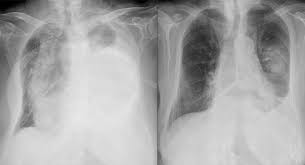

흉수(폐 바깥에 물)일 때 흔한 느낌

흉수는 폐 바깥쪽 공간에 물이 차서 폐가 눌리는 형태라, 보통은 서서히 숨이 차는 쪽이 많습니다. 초기엔 “체력이 떨어졌나?” 정도로 시작했다가 점점 불편해지기도 해요.

흉수는 원인(폐렴, 심장질환, 간·신장 질환, 다른 염증/종양 등)에 따라 동반 증상이 달라질 수 있어 “숨참 + 열” 또는 “숨참 + 체중감소”처럼 같이 나타나는 신호를 같이 보는 게 중요합니다.